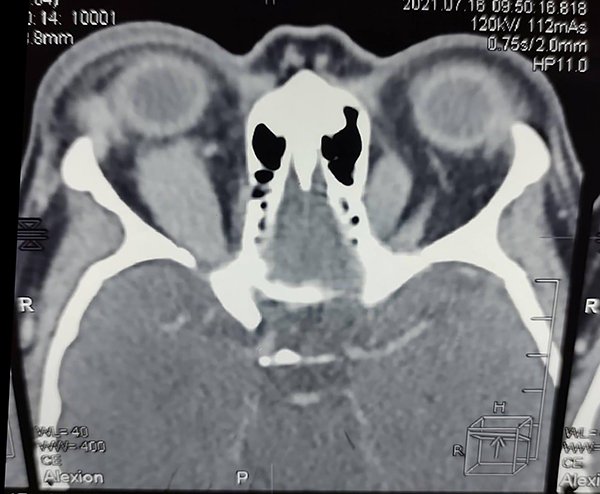

La TAC de órbita con cortes coronal y axial mostraba una masa a nivel del recto superior y oblicuo mayor derechos intraconal (figs. 6 y 7).

Figura 7. TC de órbita, corte axial: engrosamiento de los músculos recto superior y oblicuo mayor derechos.